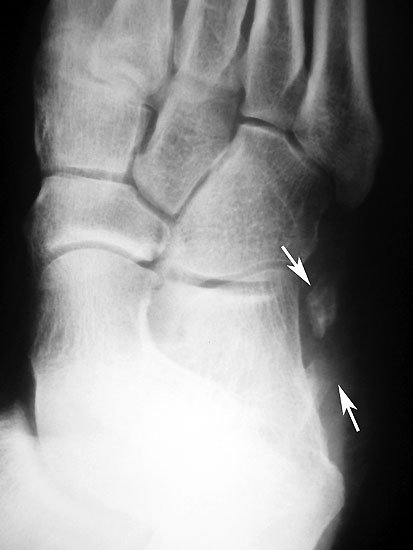

Frakturiertes Os peroneale. Das proximale Fragment ist am Fußaußenrand neben dem Calcaneus erkennbar, das distale Fragment liegt noch in Höhe des Cuboidtunnels.

Abbildung 5

Die klassischen Röntgenaufnahmen des Sprunggelenks in zwei Ebenen und des Fußes in drei Ebenen unter Belastung dienen vor allem dem Ausschluss der verschiedenen Differentialdiagnosen. Weiterhin können knöcherne Verletzungen der Gleitrinne oder auch eine Ruptur der Peroneaus longus Sehne mit disloziertem Os peroneum dargestellt werden. Besteht der Verdacht auf ein kleineres Knochenfragment oder besteht gleichzeitig eine Fraktur, so kann in Ergänzung ein hochauflösendes CT durchgeführt werden 7.